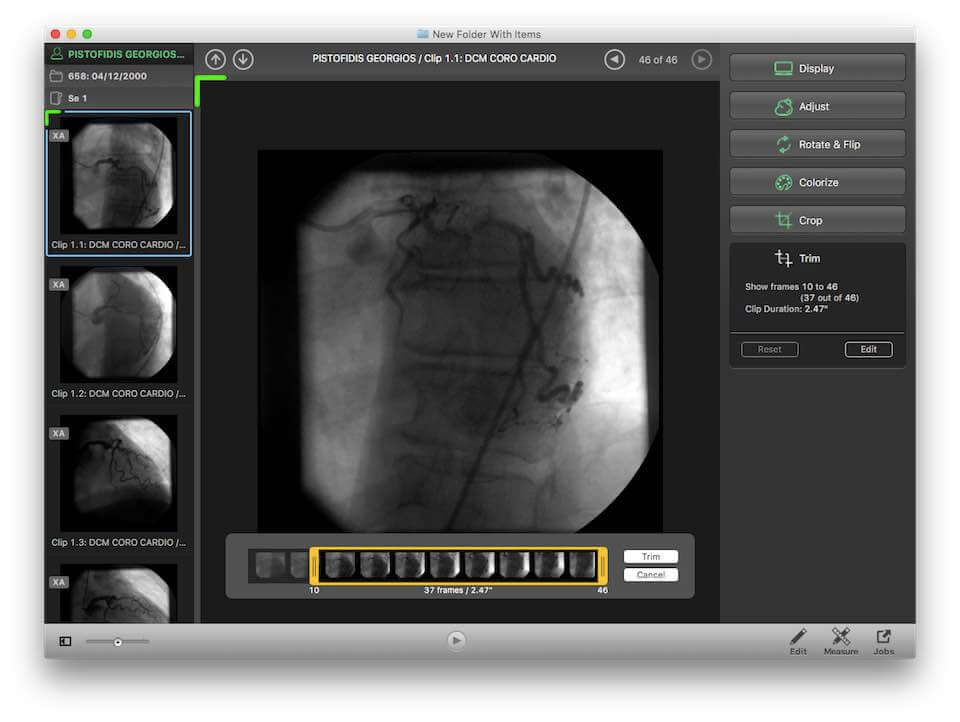

Лазерная камера для печати медицинских изображений на пленке стандарт dicom